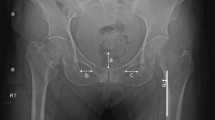

PFF with the AFF morphology was defined as a case meeting the following 2 conditions (Fig. 1): (1) An artificial hip joint implant is placed in the proximal femur. (2) Meeting at least 4 items of the major features following the definition of AFF established by JBMR in 2013 (periprosthetic femoral fractures are not excluded). The subjects were patients with APFF injured between January 1, 2008, and December 31, 2017. The control group was comprised of patients with typical PFF of our facility injured in the same period. The survey items were patient background (the age at the time of the first total hip arthroplasty, age at the time of fracture, sex, body mass index (BMI), existing disease, presence or absence of the use of cement in existing implant, and fracture region), history and period of the use of drugs for the treatment of osteoporosis, treatment method, and complications. Each group was confirmed by reviewing medical records.

Atypical periprosthetic femoral fractures (APFF) (A) Incomplete fracture with uncemented stem inserted (arrowhead: localized periosteal reaction of the lateral cortex). (B) Progression from lateral cortex reaction to full periprosthetic femoral fracture. (C) APFF with uncemented stem inserted (arrowhead: localized periosteal reaction of the lateral cortex). (D) APFF with cemented stem inserted (arrowhead: localized periosteal reaction of the lateral cortex).